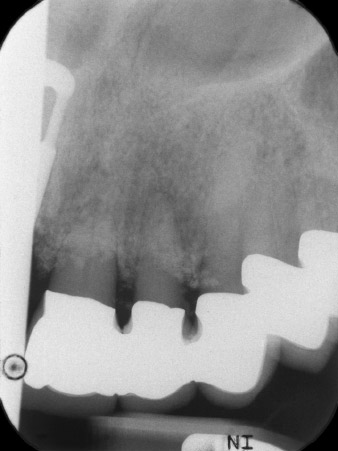

En la primera visita se trataron las piezas 21, 22 y 23, que presentaban bloqueo en las coronas colocadas hacía 19 años. Estas estaban unidas mediante una férula con los implantes de las posiciones 12/11 (figura 2). La imagen radiológica muestra una pérdida ósea horizontal alrededor de las piezas dentales 21 y 22 (figura 1).